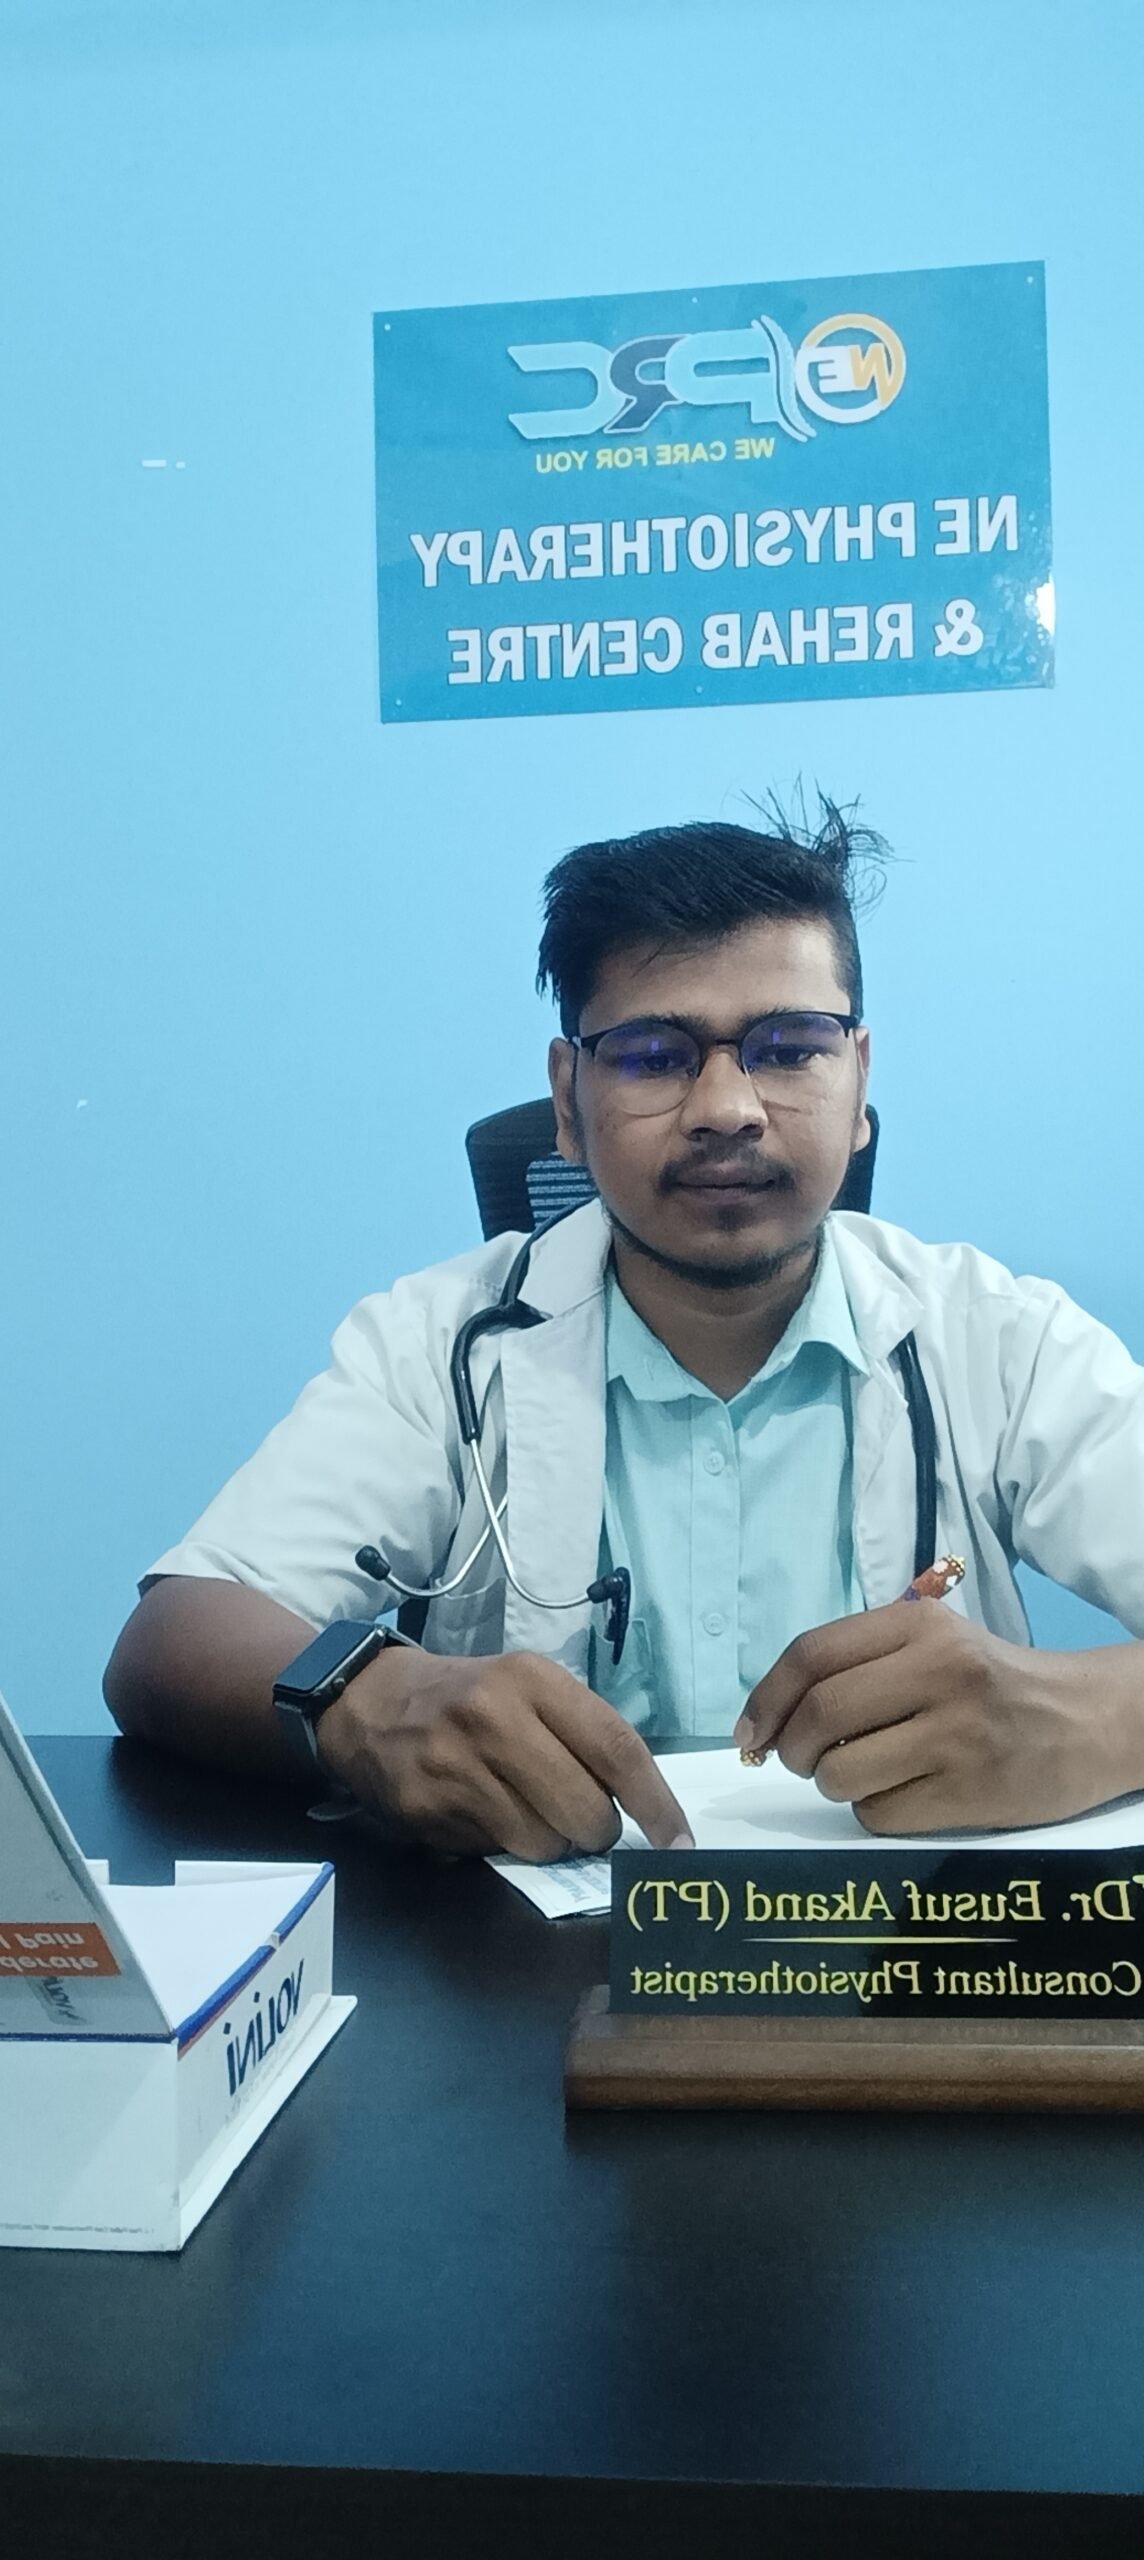

North East Physiotherapy & Rehab Centre (NEPRC) is the top physiotherapy centre in Beltola, Guwahati. At NEPRC, we offer a diverse range of services faithfully designed to your unique needs. Whether you’re recovering from an injury, seeking relief from pain & illness, or aiming to optimize your physical well-being, our team of dedicated professionals is committed to providing therapeutic excellence.